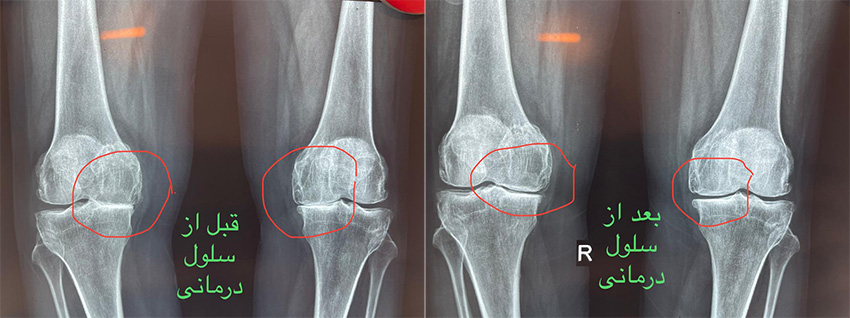

سلول درمانی زانو قبل و بعد

چندین مطالعه و کارآزمایی بالینی نشان داده اند که تزریق داخل مفصلی سلول های بنیادی مزانشیمال می تواند در بهبود عملکرد و کاهش درد در بیماران مبتلا به آرتروز زانو موثر باشد. برخی نتایج شامل بهبود نمرات درد، افزایش محدوده حرکتی مفصل و بازسازی قسمتی از غضروف آسیب دیده بوده است.